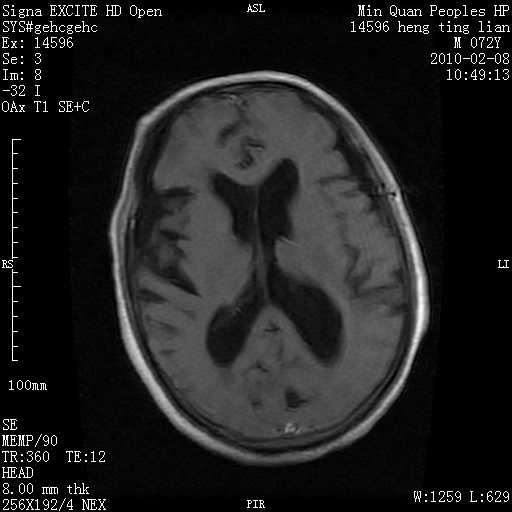

m,72,头疼,头晕两年,伴视力模糊三月,饮食呛咳两天。pe:颈部抵抗,左眼突出,左眼瞳孔约3mm,对光反射消失,双眼失明,伸舌困难,双肺呼吸音粗,心率110次/分,左上肢肌力i级,左下肢屈曲,肌张力高。现有08年2月19mri平扫及10年2月8日mri增强请会诊。ct病灶呈低密度伴散在点、片状等密度区,无明确钙化(无ct片资料可供上传)。[

脑外肿瘤,囊实性,环状不规则强化,内听道扩大,考虑神经源性肿瘤

左侧桥小脑区占位伴梗阻性脑积水----考虑 1神经鞘瘤 2室管膜瘤。

左侧桥小脑区神经鞘瘤伴梗阻性脑积水。

脑外肿瘤,病灶呈匍匐蔓延,表皮样囊肿可能性大。